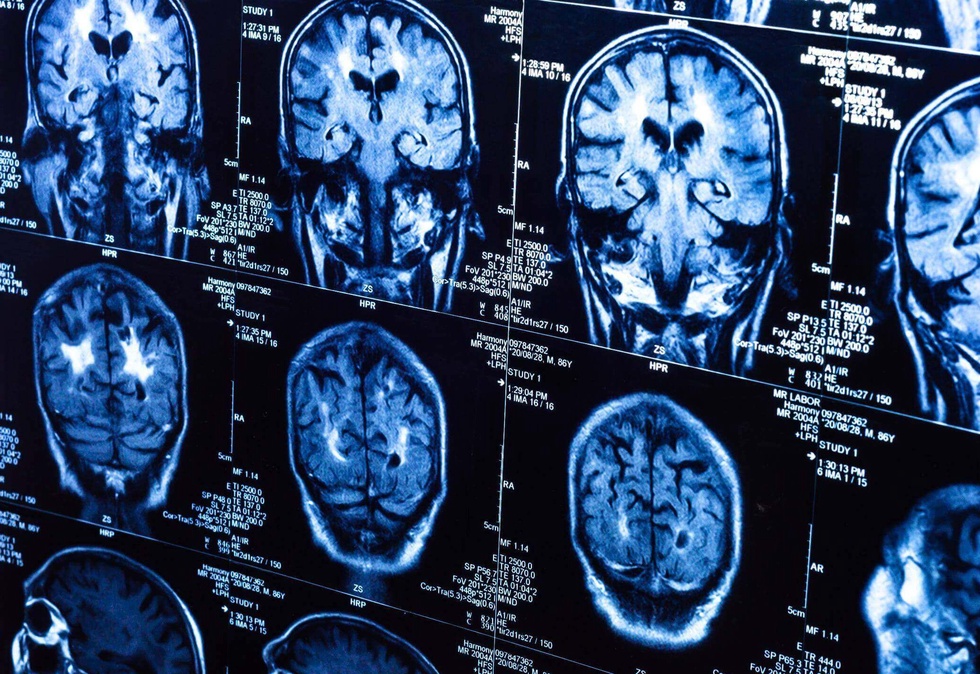

Лаборатория сичқонлари устида ўтказилган тажрибалар шуни кўрсатдики, ўсмаларни даволаш учун дори воситасини ўз ичига олган нанозаррачалар муҳим органларга салбий таъсир кўрсатмасдан мияда бир неча соат давомида муваффақиятли тўпланади.

Бу стратегия мия саратонини даволаш ва касалликнинг қайта пайдо бўлишининг олдини олишнинг янада самарали усули бўлиши мумкин. Клиникадан олдинги тадқиқотлар истиқболли тиббий технологияларнинг ривожланишини тезлаштиради ва ана шундай ташхис қўйилган беморларнинг аҳволини яхшилашга ёрдам беради.